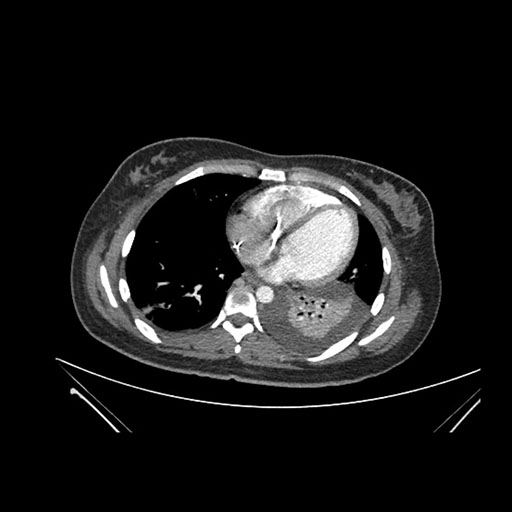

Imaging Analysis

Look through the patient's CT scan to identify any areas of concern for the necessary procedure.

Coronal Arterial

Based on initial findings, which issue(s) would you be most concerned about?